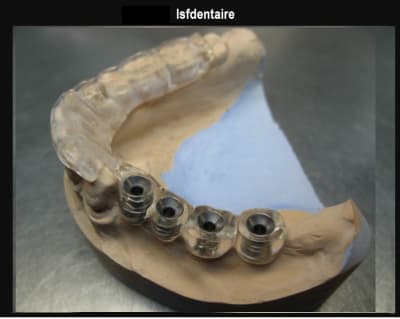

exemple de guide, pour quasi le meme cas : guide resine a apuis dentaire muqueux VS guide appuis dentaire/ osseux.

Avantage posit sans aucun doute sur la ridgidité et la pose de l'implant le plus distal...